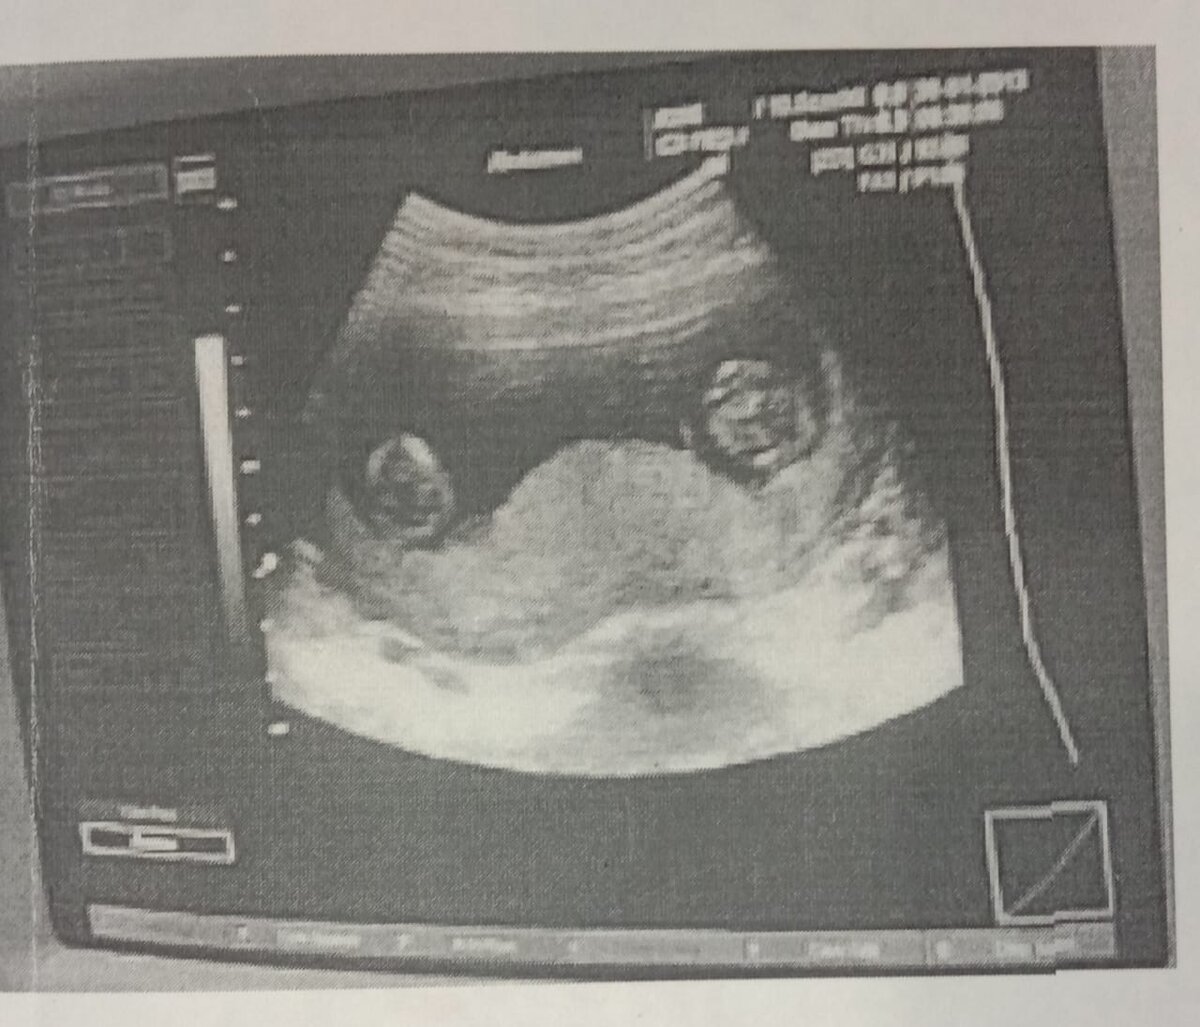

Когда я узнала, что стану мамой #двойни, честно скажу, была несколько обескуражена... Сын у меня к тому времени уже был, хотелось еще лапочку- дочку. И тут на тебе...Ну не была я готова к такому положению вещей. Я смеялась, плакала, настроение никак не находило какую сторону принять...Реакция мужа поразила меня еще больше. Когда я вышла из больницы с результатом #УЗИ, он ждал меня на улице.

наше первое фото)))